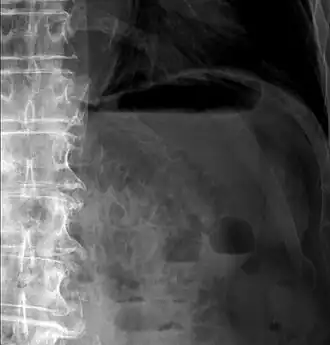

Pneumatosis intestinalis (also called intestinal pneumatosis, pneumatosis cystoides intestinalis, pneumatosis coli, or intramural bowel gas) is pneumatosis of an intestine, that is, gas cysts in the bowel wall.[1][2] As a radiological sign it is highly suggestive for necrotizing enterocolitis. This is in contrast to gas in the intestinal lumen (which is relieved by flatulence). In newborns, pneumatosis intestinalis is considered diagnostic for necrotizing enterocolitis, and the gas is produced by bacteria in the bowel wall.[3] The pathogenesis of pneumatosis intestinalis is poorly understood and is likely multifactorial. PI itself is not a disease, but rather a clinical sign. In some cases, PI is an incidental finding, whereas in others, it portends a life-threatening intra-abdominal condition.